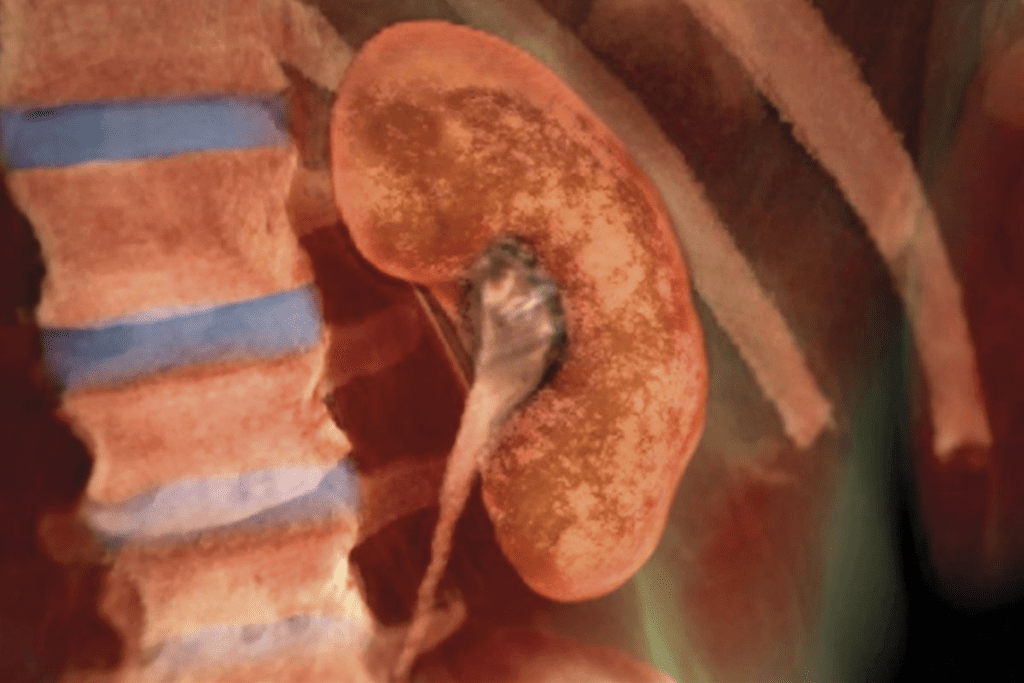

Normal Kidney Anatomy on Ultrasound

A normal ultrasound shows kidneys that are symmetrical and smooth. The outer layer, called the renal cortex, looks uniform. The renal sinus, with the renal pelvis and blood vessels, is also seen.

The size and brightness of the kidneys on the ultrasound are important. They show if your kidneys are healthy.

Ultrasound Appearance of Normal vs. Damaged Kidneys

Ultrasound imaging is key in telling normal from damaged kidneys. It’s a non-invasive way to check kidney health. Healthcare pros use it to look at kidney structure and spot any issues.

Characteristics of Healthy Kidneys

A normal kidney ultrasound shows a kidney with a smooth shape and even texture. It also has a clear difference between the cortex and medulla. Healthy kidneys are usually 9-12 cm long and look like a bean.

The renal cortex is isoechoic or slightly hyperechoic compared to the liver. The renal sinus, with its fat and blood vessels, is hyperechoic. Knowing these details helps spot any kidney issues.